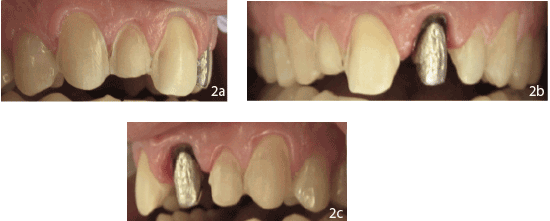

单板的准备

使用金刚石钻从第6、7、8、10、11颗牙齿上去除现有的贴面,并按照牙齿表面的轮廓进行准备,尽量保留牙釉质。颈缘延伸至牙龈嵴,以与整个龈缘平行的肩线结束。这条终点线在近端间继续,并与相邻的牙齿保持齐平。贴面包裹在舌侧的切缘上。任何尖锐的线角都用优质的钻石钻磨圆(图2a-2c)。

图1:a)术前右侧位视图b):术前正位视图c):术前左侧位视图d):术前上颌咬合视图

皇冠准备

在移除9号牙的现有冠后,存在一个金属铸造桩和核,并有复发龋坏。龋齿是用圆形钻子挖出来的。临床判断是保持桩核完整,因为之前的根管治疗无症状,并将边缘改善至90度肩缘,延伸至牙龈下(图2b-c)。

图2:a)术后右侧视图b):术后正面视图c):术后左侧视图d):术后上颌视图